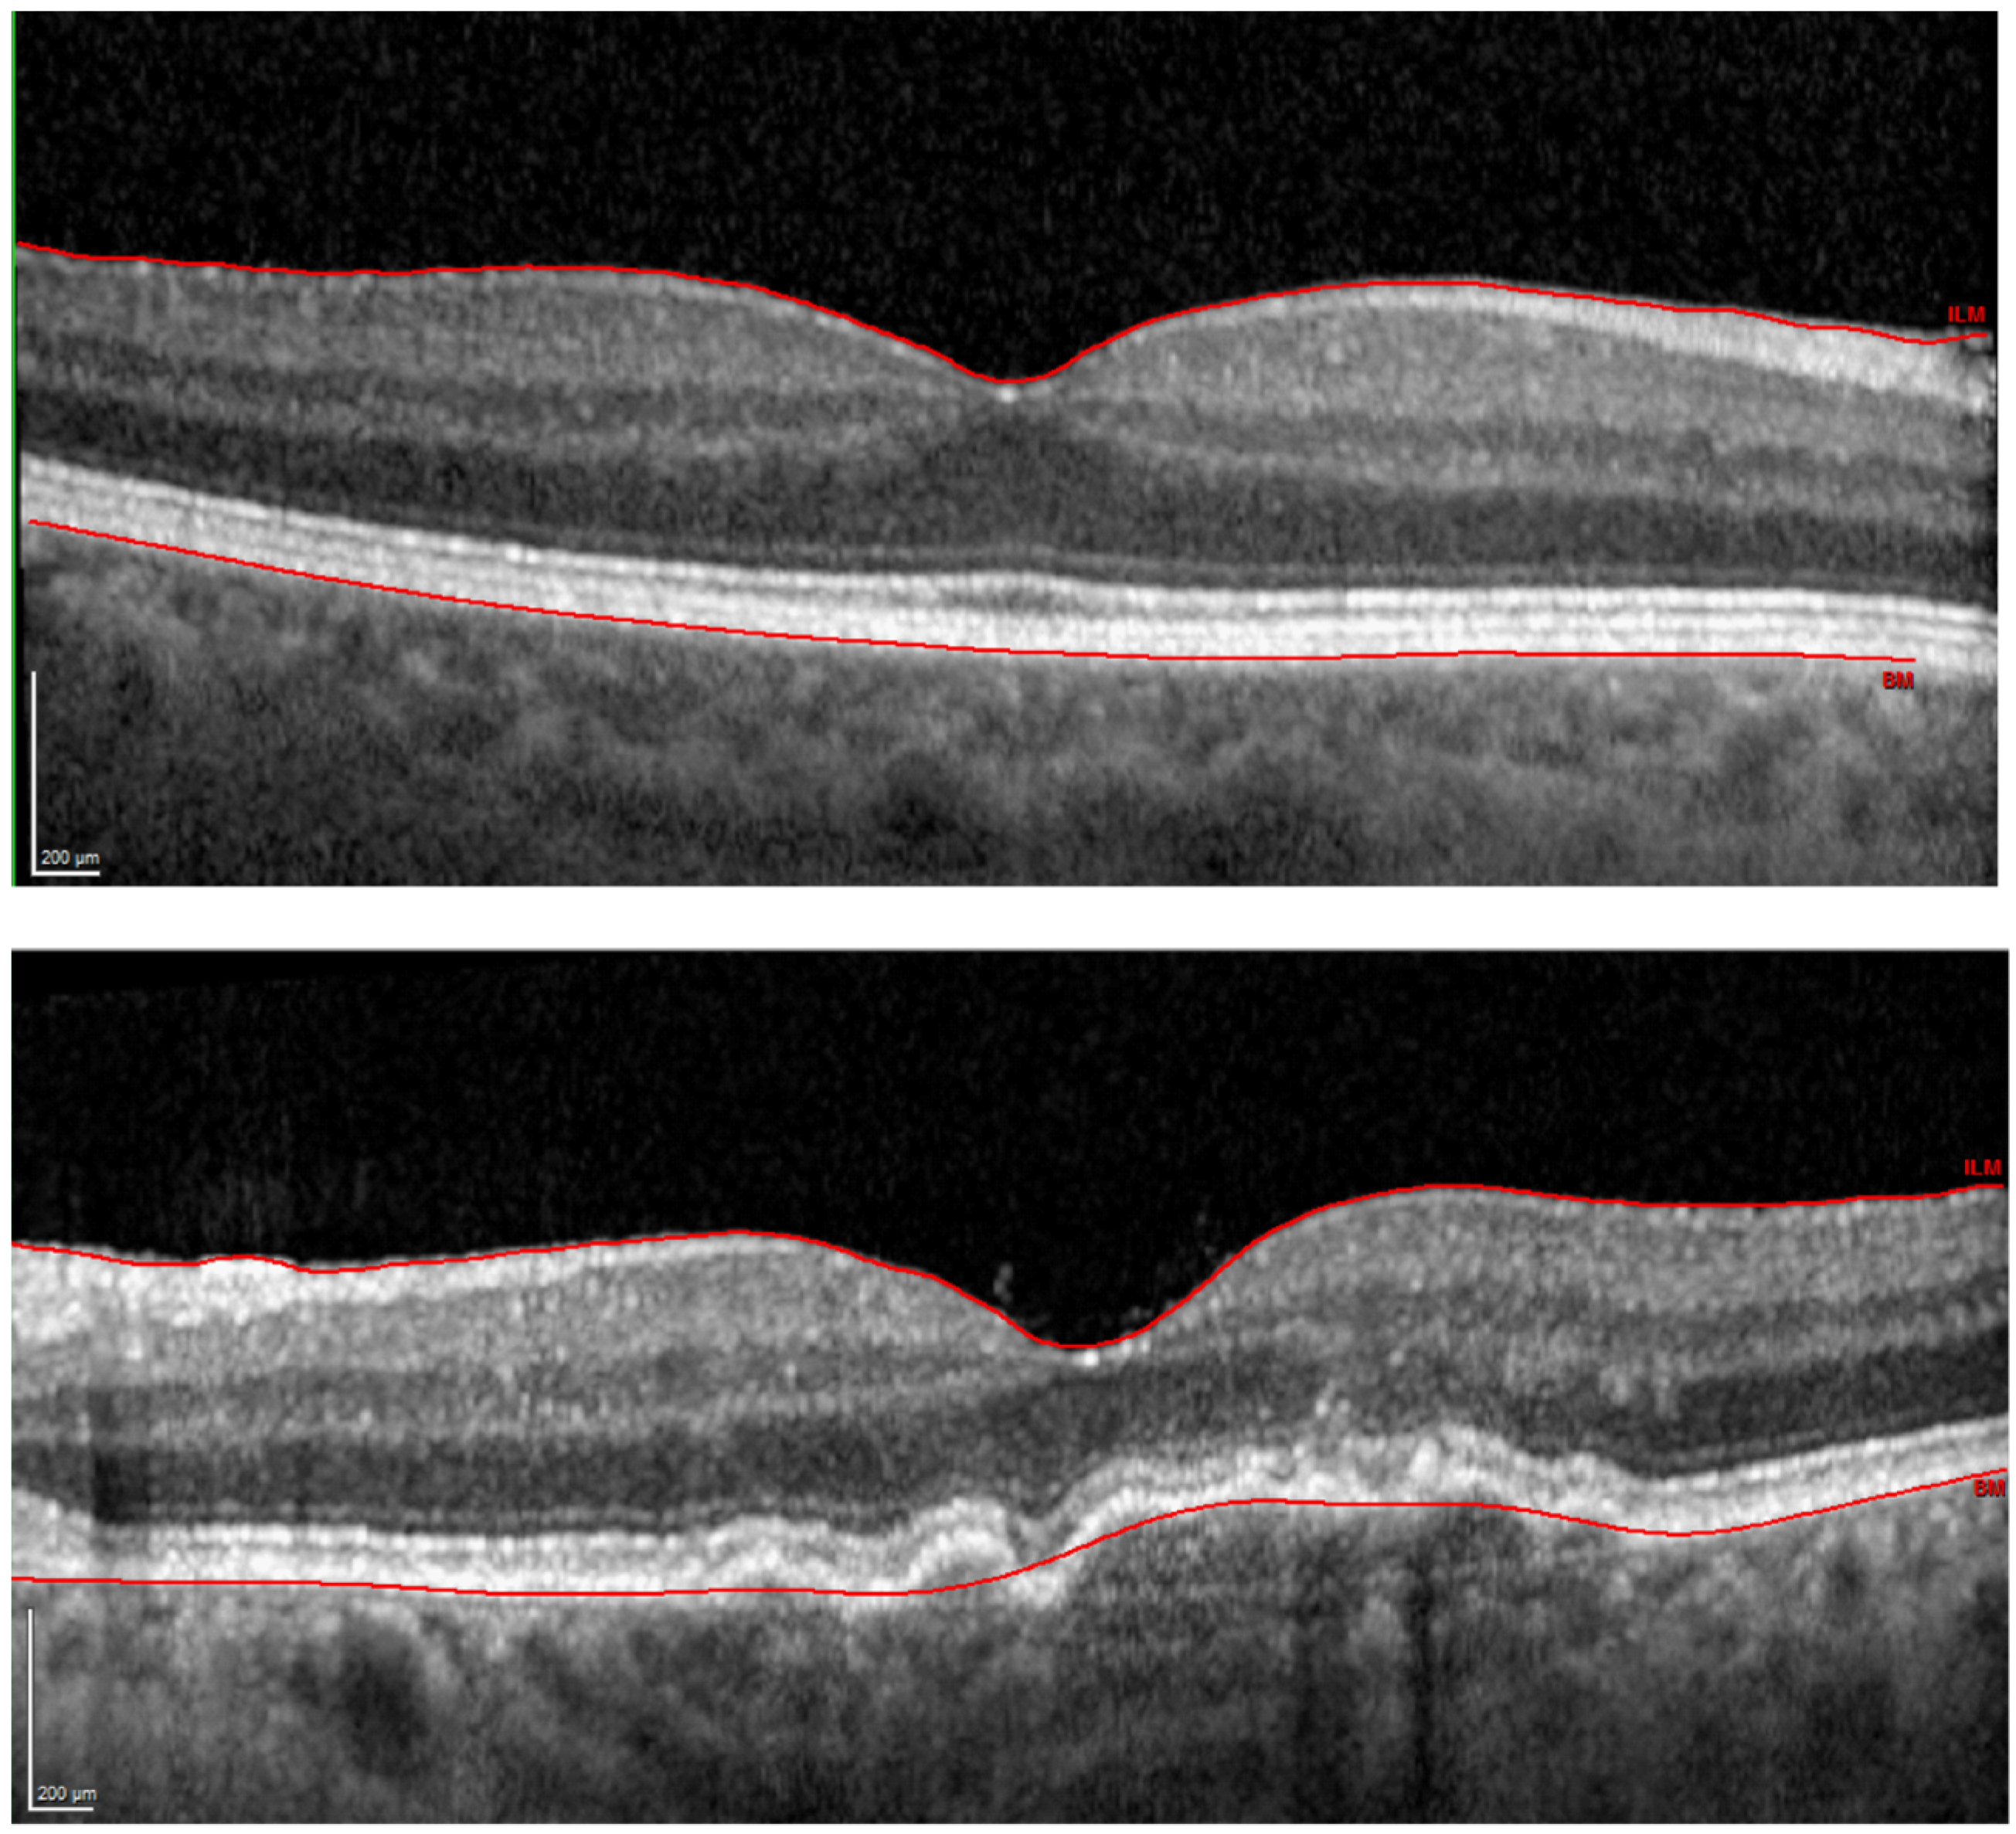

Following successful enrollment based on subjects’ medical history, monocular best-corrected VA (BCVA) was assessed using an Early Treatment Diabetic Retinopathy Study (ETDRS) chart placed at 4 m. The logarithm of the straylight parameter, i.e., log(s), was measured using a C-Quant device (Oculus GmbH, Wetzlar, Germany) to quantify ocular turbidity [17]. Next, OCT with Spectralis (Heidelberg Engineering GmbH, Heidelberg, Germany) was performed after pupil dilation with 5 mg/mL tropicamide (Pharma Stulln GmbH, Stulln, Germany). A 30° scan was taken for macula assessment and the retinal thickness, which is the distance separating the internal limiting membrane and the outer surface of the RPE (Figure 1), was exported using built-in software. A comprehensive examination of the anterior segment and the fundus was conducted with a slit lamp to render patients’ eligibility for the study and grade AMD severity.

Figure 1.

Optical coherence tomography images of a representative control (upper panel) and disease (lower panel) case. The solid red line indicates the automatic retinal layer segmentation, which defines the retinal thickness.